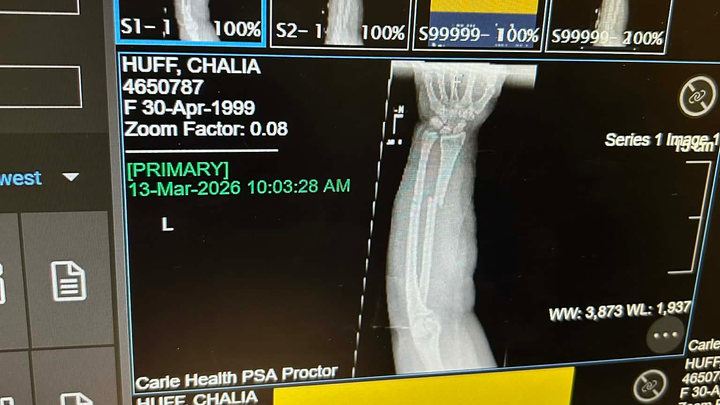

On Friday the 13th of March, I fell off of my electric bike trying to get to the bank. The fall resulted in me breaking both my radius and ulnar bones in my arm and fracturing my scaphoid bone in my wrist. During the time of my fall, I had no insurance and I’ve had to come out of pocket for my splint and sling costs, transportation to and from the doctor's offices and hospital, and overall having to overpay some not-so-good friends for help.